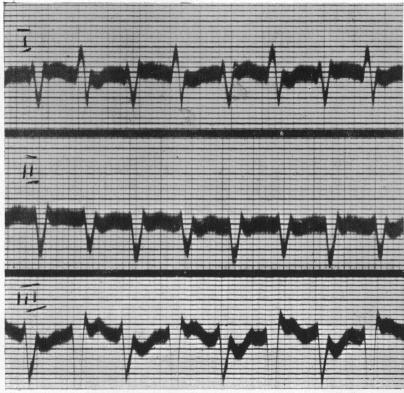

INCOMPLETE BUNDLE BRANCH BLOCK.

Br Heart J. 1944 Jul;6(3):139-48. doi: 10.1136/hrt.6.3.139.